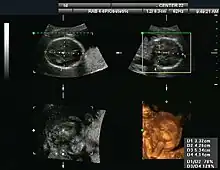

Orthogonal planes of a three-dimensional sonographic volume with transverse and coronal measurements for estimating fetal cranial volume[16][17]

Gynecologic ultrasonography examines female pelvic organs (specifically the uterus, ovaries, and fallopian tubes) as well as the bladder, adnexa, and pouch of Douglas. It uses transducers designed for approaches through the lower abdominal wall, curvilinear and sector, and specialty transducers such as transvaginal ultrasound.[18]

Obstetrical sonography was originally developed in the late 1950s and 1960s by Sir Ian Donald[19][20] and is commonly used during pregnancy to check the development and presentation of the fetus. It can be used to identify many conditions that could be potentially harmful to the mother and/or baby possibly remaining undiagnosed or with delayed diagnosis in the absence of sonography. It is currently believed that the risk of delayed diagnosis is greater than the small risk, if any, associated with undergoing an ultrasound scan. However, its use for non-medical purposes such as fetal "keepsake" videos and photos is discouraged.[21]